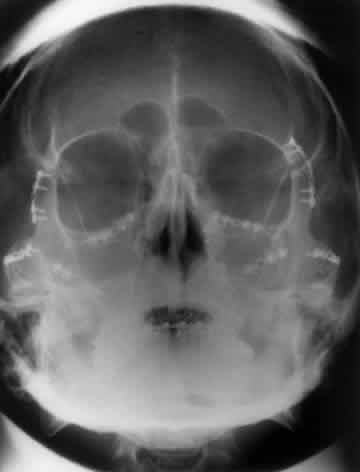

The optic foramen should measure 6 mm vertically and 5 mm horizontally. Asymmetry greater than 1 mm or a vertical dimension greater than 6.5 mm is considered abnormal.15,27 Ninety-eight percent of patients have optic canals that vary by less than 1 mm.27 Concentric enlargement of the foramen and optic canal can be seen with optic nerve gliomas, meningiomas, neurofibromatosis, and less commonly an aneurysm of the ophthalmic artery (Fig. 16). A decrease in the optic foramen and canal dimension can be seen in fibrous dysplasia, Paget's disease, hyperostosis secondary to a meningioma, or microphthalmos (Fig. 17, Table 1).

Fig. 17. Bilateral optic canal compression from fibrous dysplasia. There is diffuse bone thickening in each orbit. Note small size of optic foramen (arrow).